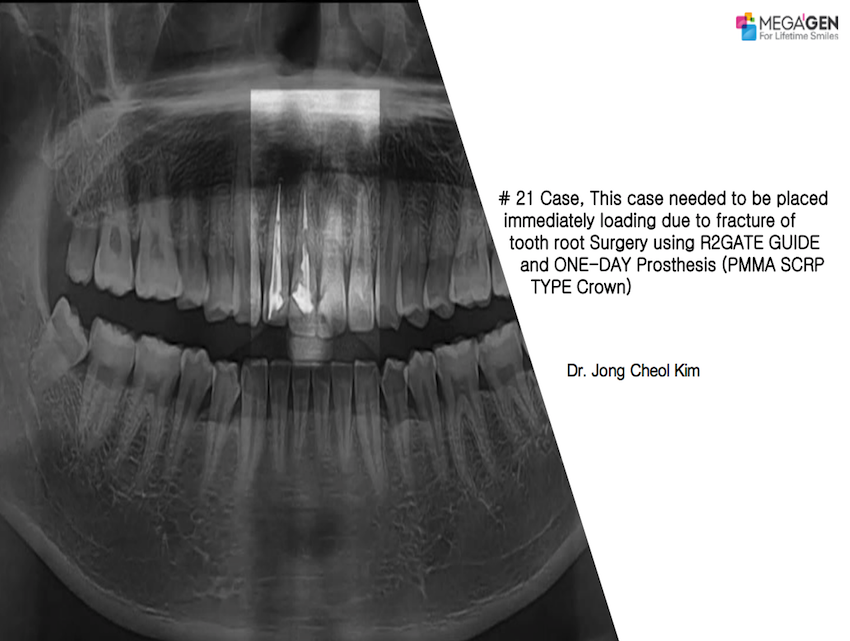

Dr. Michiko Noguchi,Aesthetic Zone,Immediate loading,Maxillary Anterior,#11,#13,#21,Root Membrane,AnyRidge,MEGA ISQ,Root Membrane Kit,Poster